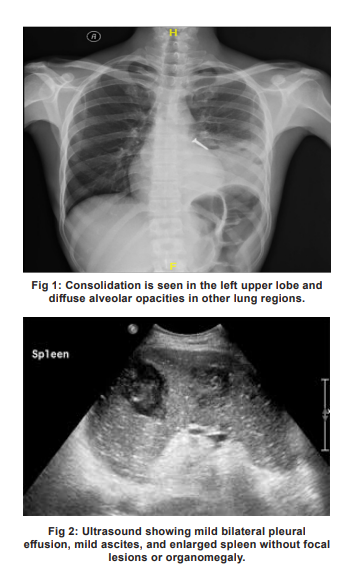

Imaging Results

Chest X-ray showed homogeneous consolidation in the left upper lobe and diffuse alveolar opacities in the remaining lung fields (Fig 1). The ultrasound revealed mild bilateral pleural effusion, mild ascites, and enlarged spleen without focal lesions or organomegaly (Fig 2). Brain biopsy results are depicted in Fig 3.